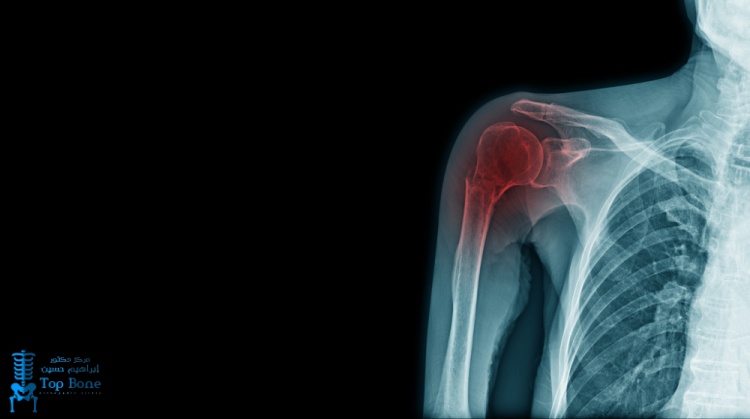

تعد عملية تثبيت الكتف إجراء جراحي يهدف إلى علاج عدم استقرار مفصل الكتف الناتج عن تمزق أو ضعف الأنسجة والأربطة المسؤولة عن ثباته ويوصى بهذا التدخل في حالات الإصابات الرياضية، وتكرار خلع أو التواء الكتف، أو بعض المشكلات المرضية التي تؤثر على استقرار المفصل ويعتبر التثبيت الجراحي حل فعال لاستعادة ثبات الكتف وتحسين كفاءته الوظيفية.

عملية تثبيت الكتف

يعتمد الإنسان على مفصل الكتف في العديد من الأنشطة اليومية، مثل حمل الأوزان الثقيلة وممارسة التمارين الرياضية، وذلك بفضل مجموعة من العضلات والأوتار التي تمنح المفصل مرونة الحركة في مختلف الاتجاهات.

ماهي أسباب عدم استقرارية الكتف

توجد عدة أسباب تؤدي إلى عدم استقرار مفصل الكتف، ومن أبرزها ما يلي:

- الإصابات الرياضية: قد تتسبب الرياضات العنيفة مثل كرة القدم أو رفع الأثقال في حدوث تمزق بالأربطة الكتفية نتيجة الصدمات القوية.

- الالتواءات المتكررة: تكرار التواء أو خلع الكتف يؤدي مع الوقت إلى ضعف وتلف الأربطة، مما يزيد من فقدان استقرار المفصل.

- الأمراض الوراثية: يعاني بعض الأشخاص من عوامل وراثية تجعل أربطة الكتف لديهم أكثر عرضة للارتخاء وعدم الثبات.

- التقدم في العمر: مع التقدم في السن، تتعرض الأنسجة والأربطة للتآكل والضعف التدريجي، مما يرفع احتمالية عدم استقرار الكتف.